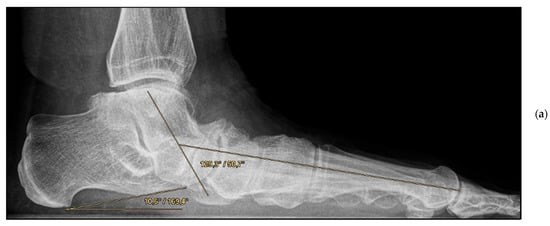

Figure 3.

Pre- and post-operative radiographic findings of combined talonavicular arthrodesis and calcaneal displacement osteotomy, left foot. (a) Lateral view pre-operative, (b) lateral view post-operative.

Medial calcaneal displacement osteotomy and talonavicular arthrodesis (Group A). In the first step, a V-shaped osteotomy was performed via an oblique approach to the lateral calcaneus with medial displacement of the back portion of the calcaneus. Osteotomy was performed using either an oscillating bone saw or bone chisel. Depending on the extent of the deformity, a medial displacement of approximately 8–10 mm was considered optimal. Fixation was achieved by means of two percutaneously inserted lag screws with diameters of 4.0–6.5 mm. The second step was talonavicular arthrodesis via a dorsal approach, usually with interposition of an iliac crest bone graft. Fixation was performed using two or three screws with diameters of 4 mm or a combination of screws and Nitinol compression implants (Figure 2a,b and Figure 3a,b).